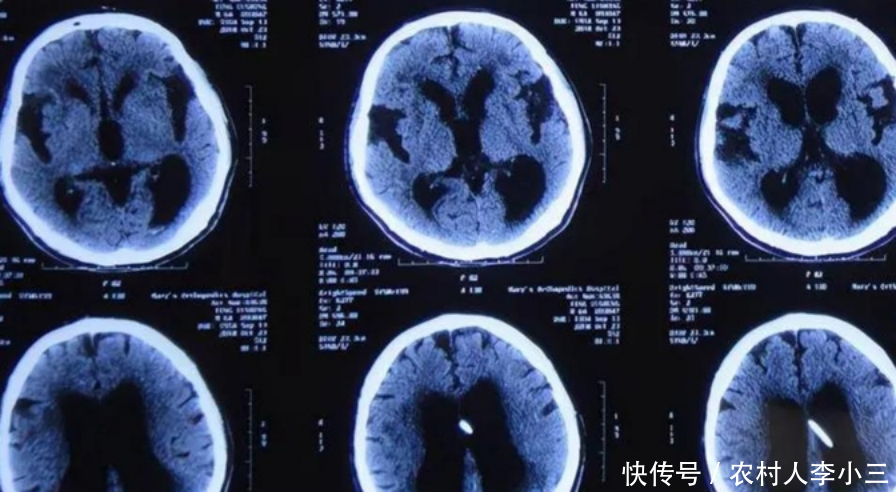

大脑开始“萎缩”,身体一般会出现4个反应,要提前预防